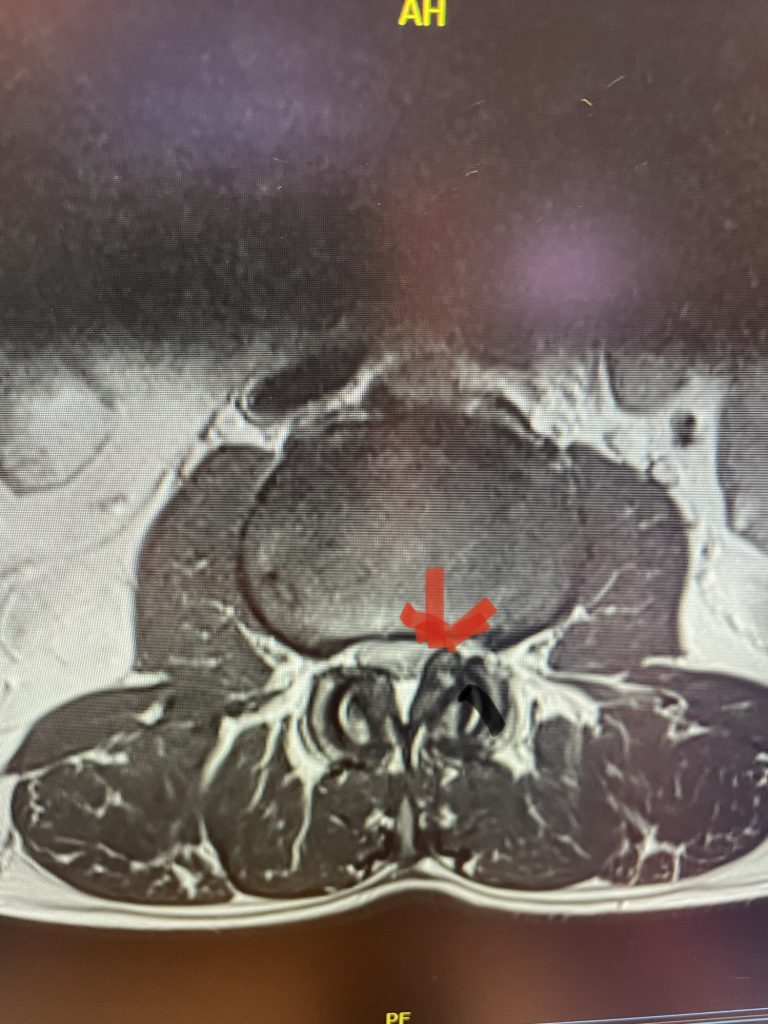

This 71 year-old male presents with a long history of progressive pain in the low back with radiation to both legs in the anterior thigh distribution, the left being worse than the right. He feels that his legs get weak. Standing and walking worsen the low back pain and lower extremity symptoms while sitting relieves the symptoms. He failed PT and epidural injections. Imaging studies revealed severe lateral recess stenosis do mainly to severed thickened ligament. He had severe lateral recess stenosis from L2-5 (Fig 4) as well as central stenosis. He also had a slight retrolisthesis at L3-4 and L4-5. He had on the left in particular a very enlarged protruded segment of thickened ligamentum in the subarticular recess at L3-4 (Fig 5) which was likely responsible for his left leg pain as the patient had symptoms of an L4-type syndrome. It was decided to perform a decompressive laminectomy from L2-5. Because of retrolisthesis it was decided to perform a noninstrumented onlay bone fusion or an in situ fusion from L3-5. In this case it was very important to decompress not only the thecal sac, but also the lateral recess with the thickened ligament at the point where the nerve makes its course into the forman. As a surgeon you must really undercut the facet joints to clear the lateral recess and feel how the nerve root with one’s instrument is being released as it enters the foramen. Postoperatively the patient had resolution of his leg pain, particularly on the left. In this case the most significant pathology was in the left L3-4 lateral recess, his symptoms and MRI findings correlated well which leads to the most successful operations.

Figure 5: Axial T2-weighted MRI demonstrating severe bilateral lateral recess stenosis secondary to thickened ligamentum flavum. Notice the prominence of the left ligamentum in the subarticular recess.